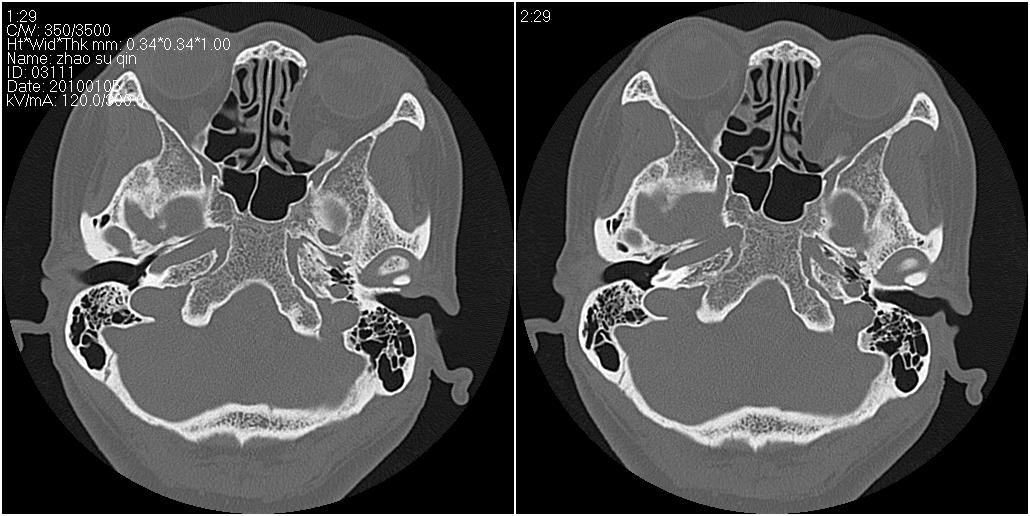

标题: CT24015:一个头部外伤患者进行鉴定,除了左侧筛板骨折,哪 [打印本页]

标题: CT24015:一个头部外伤患者进行鉴定,除了左侧筛板骨折,哪

左眶下裂部好像有骨折 似有小碎骨片

1)左侧筛板骨折。2)双侧筛窦炎症(或积血)。